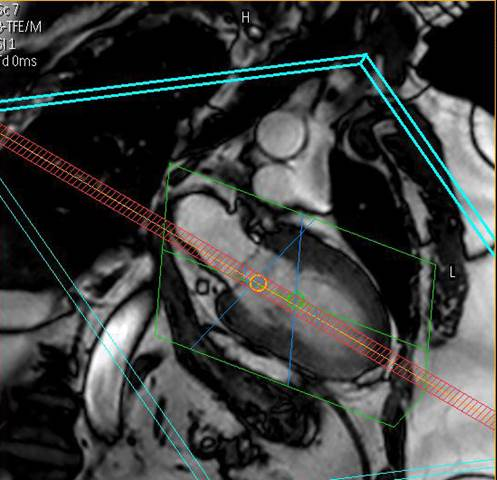

Equipment

Wir bieten modernste MRT-Diagnostik.

Ganzkörper MR System - Philips healthcare